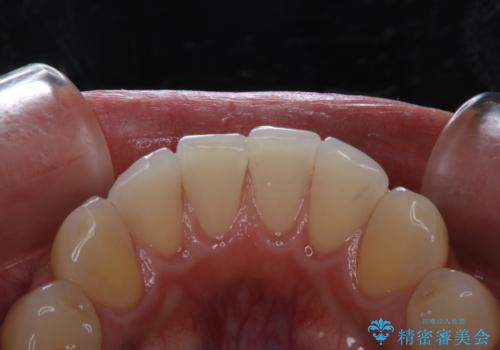

電子タバコによる着色をPMTCできれいに落とす

- 1日に10本くらい電子タバコを吸うため、歯の黄ばみ・着色が気になるとのことでした。PMTC30分コースを行いました。

PMTCでは、歯の表面の凸凹にミネラルを補給して、ツルツルの表面に仕上げます。定期的にPMTCを行うことにより、歯質の強化になり着色がつきにくい状態になります。